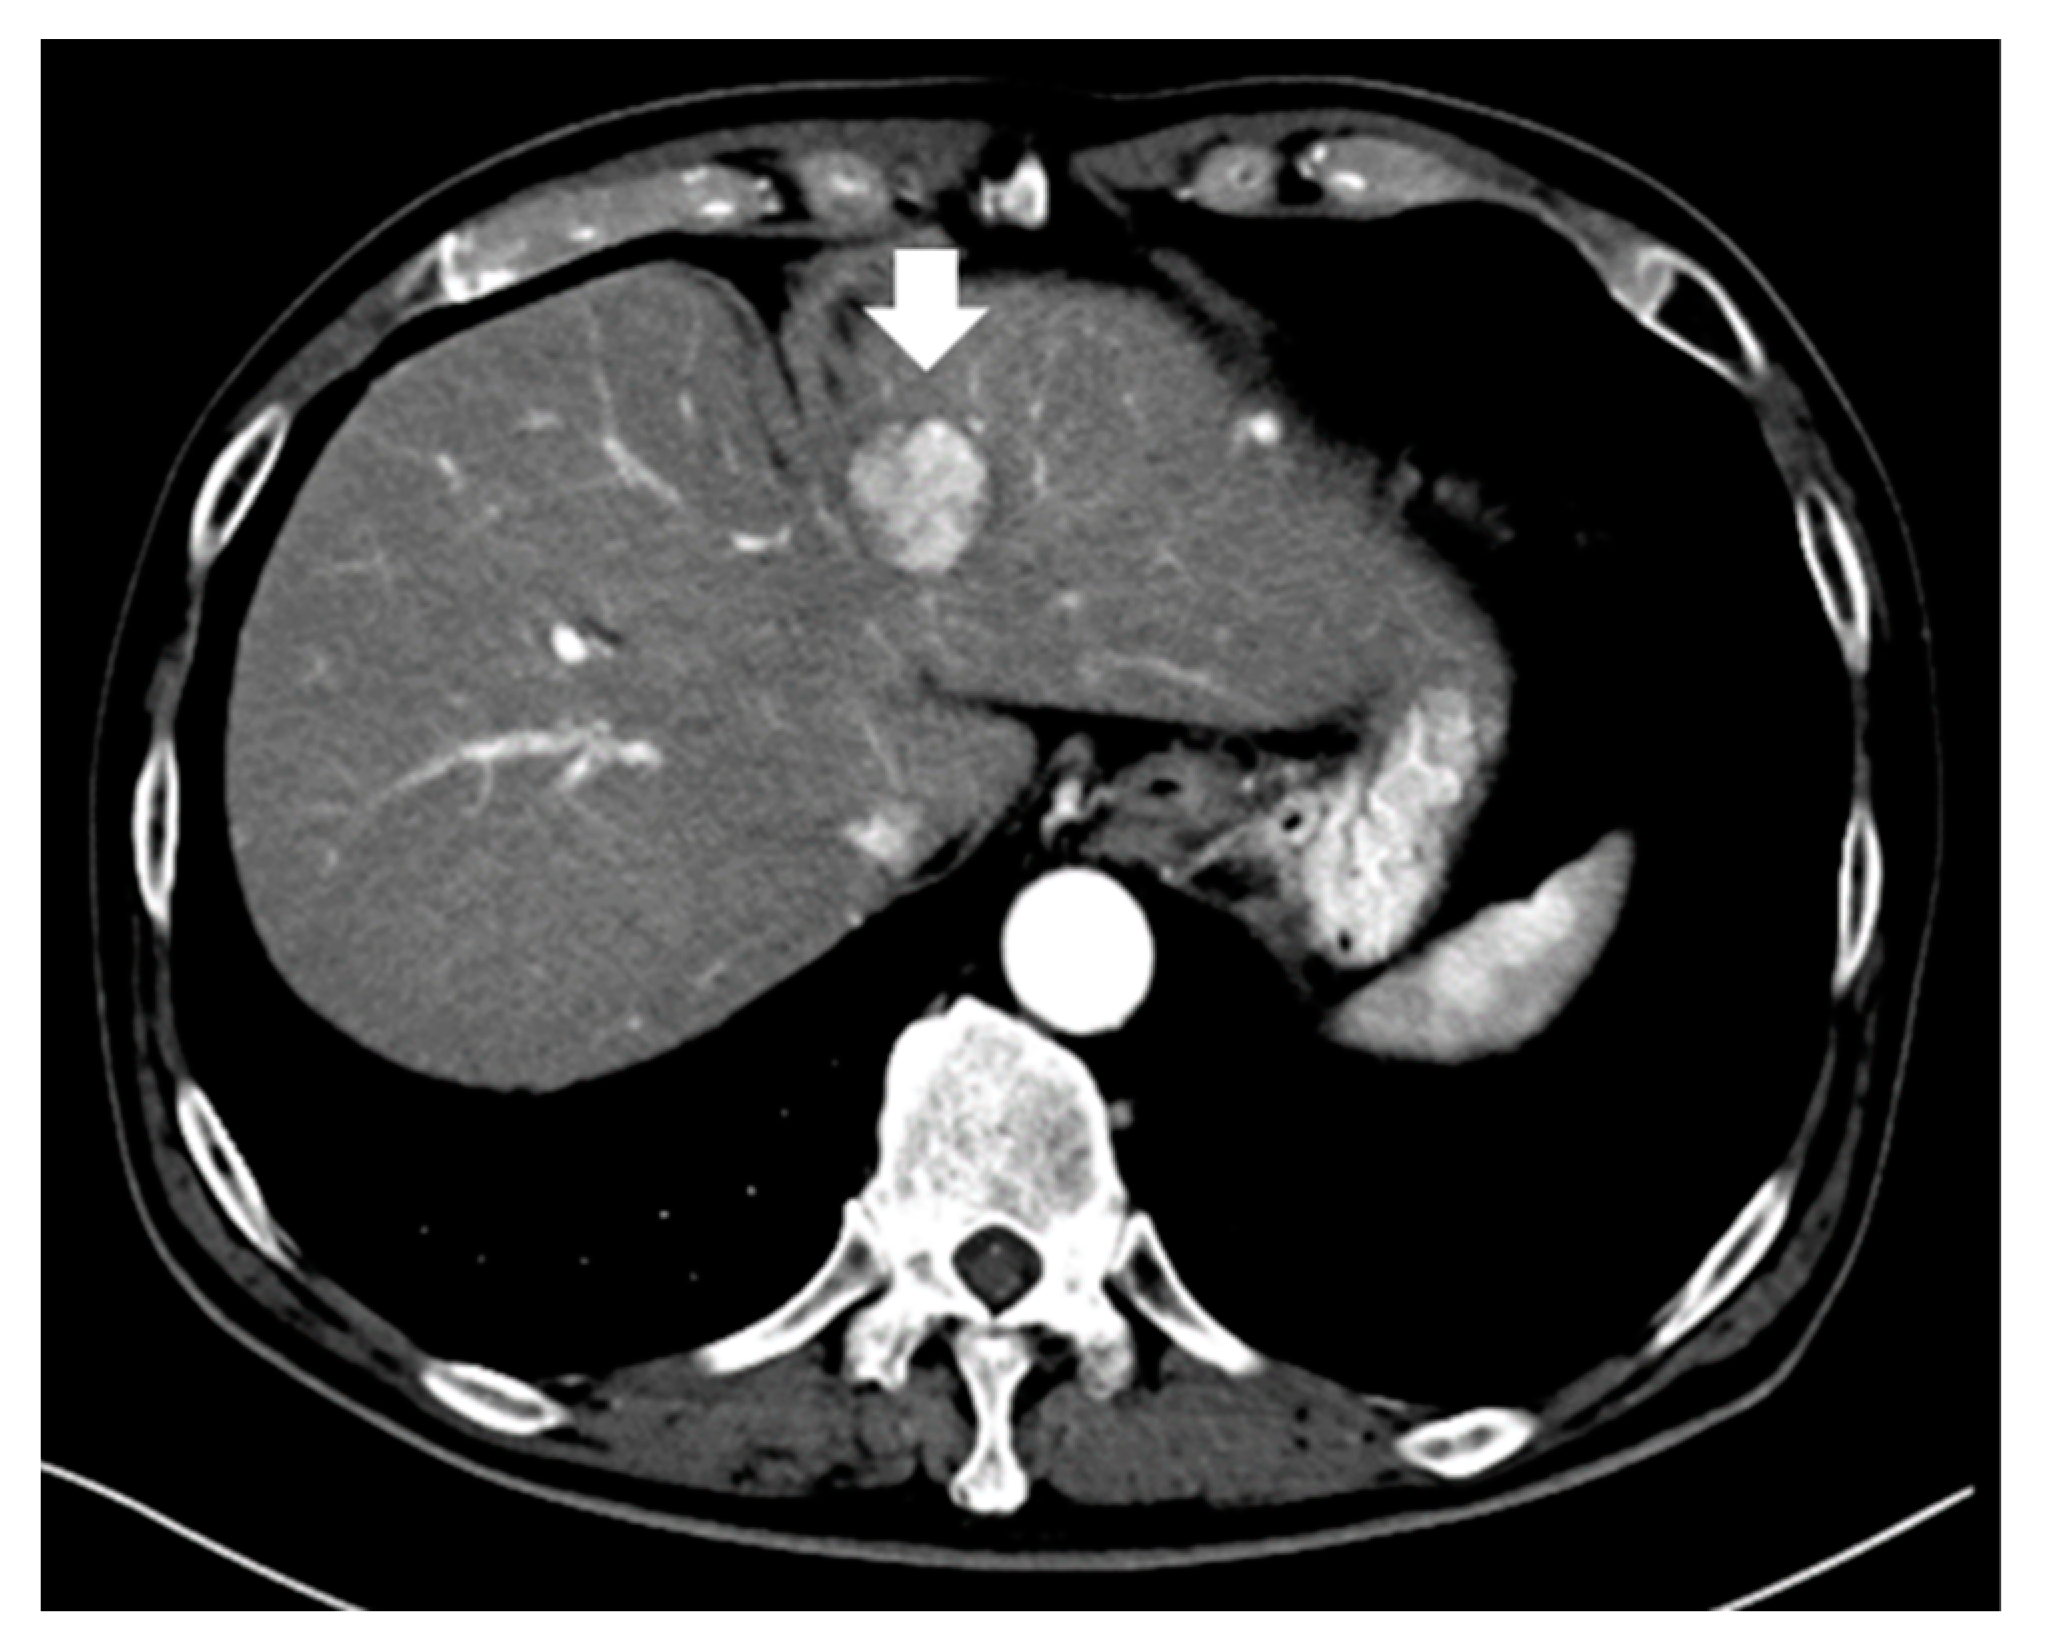

3.1. Enhancement Pattern in the Arterial Phase

3.2. Intratumoral Arteries and Enhancement Pattern

- Kawamura, Y.; Ikeda, K.; Hirakawa, M.; Yatsuji, H.; Sezaki, H.; Hosaka, T.; Akuta, N.; Kobayashi, M.; Saitoh, S.; Suzuki, F.; et al. New classification of dynamic computed tomography images predictive of malignant characteristics of hepatocellular carcinoma. Hepatol. Res. Off. J. Jpn. Soc. Hepatol. 2010, 40, 1006–1014. [Google Scholar] [CrossRef]

- Kawamura, Y.; Ikeda, K.; Seko, Y.; Hosaka, T.; Kobayashi, M.; Saitoh, S.; Kumada, H. Heterogeneous type 4 enhancement of hepatocellular carcinoma on dynamic CT is associated with tumor recurrence after radiofrequency ablation. AJR Am. J. Roentgenol. 2011, 197, W665–W673. [Google Scholar] [CrossRef]

- Nakachi, K.; Tamai, H.; Mori, Y.; Shingaki, N.; Moribata, K.; Deguchi, H.; Ueda, K.; Inoue, I.; Maekita, T.; Iguchi, M.; et al. Prediction of poorly differentiated hepatocellular carcinoma using contrast computed tomography. Cancer Imaging Off. Publ. Int. Cancer Imaging Soc. 2014, 14, 7. [Google Scholar] [CrossRef] [PubMed]

- Shimizu, R.; Tamai, H.; Mori, Y.; Shingaki, N.; Maeshima, S.; Nuta, J.; Maeda, Y.; Moribata, K.; Muraki, Y.; Deguchi, H.; et al. The arterial tumor enhancement pattern on contrast-enhanced computed tomography is associated with primary cancer death after radiofrequency ablation for small hepatocellular carcinoma. Hepatol. Int. 2016, 10, 328–339. [Google Scholar] [CrossRef] [PubMed]